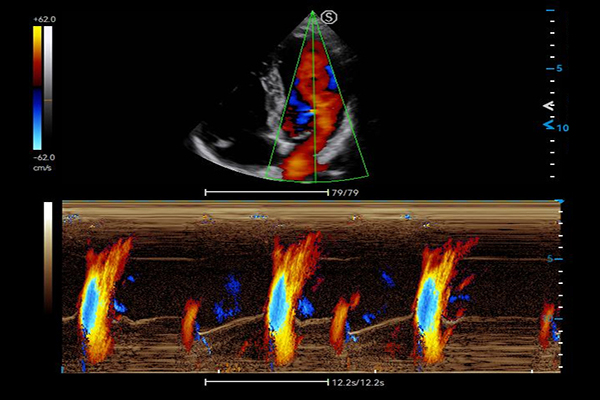

- Category: Color Doppler

VS Flow is highly sensitive to low velocity blood flow signal and especially suitable for superficial blood flow examination

Auto Flow automatically adjusts the sampling frame to better capture the blood flow signal, while Auto Fit intelligently optimizes the image display through one click